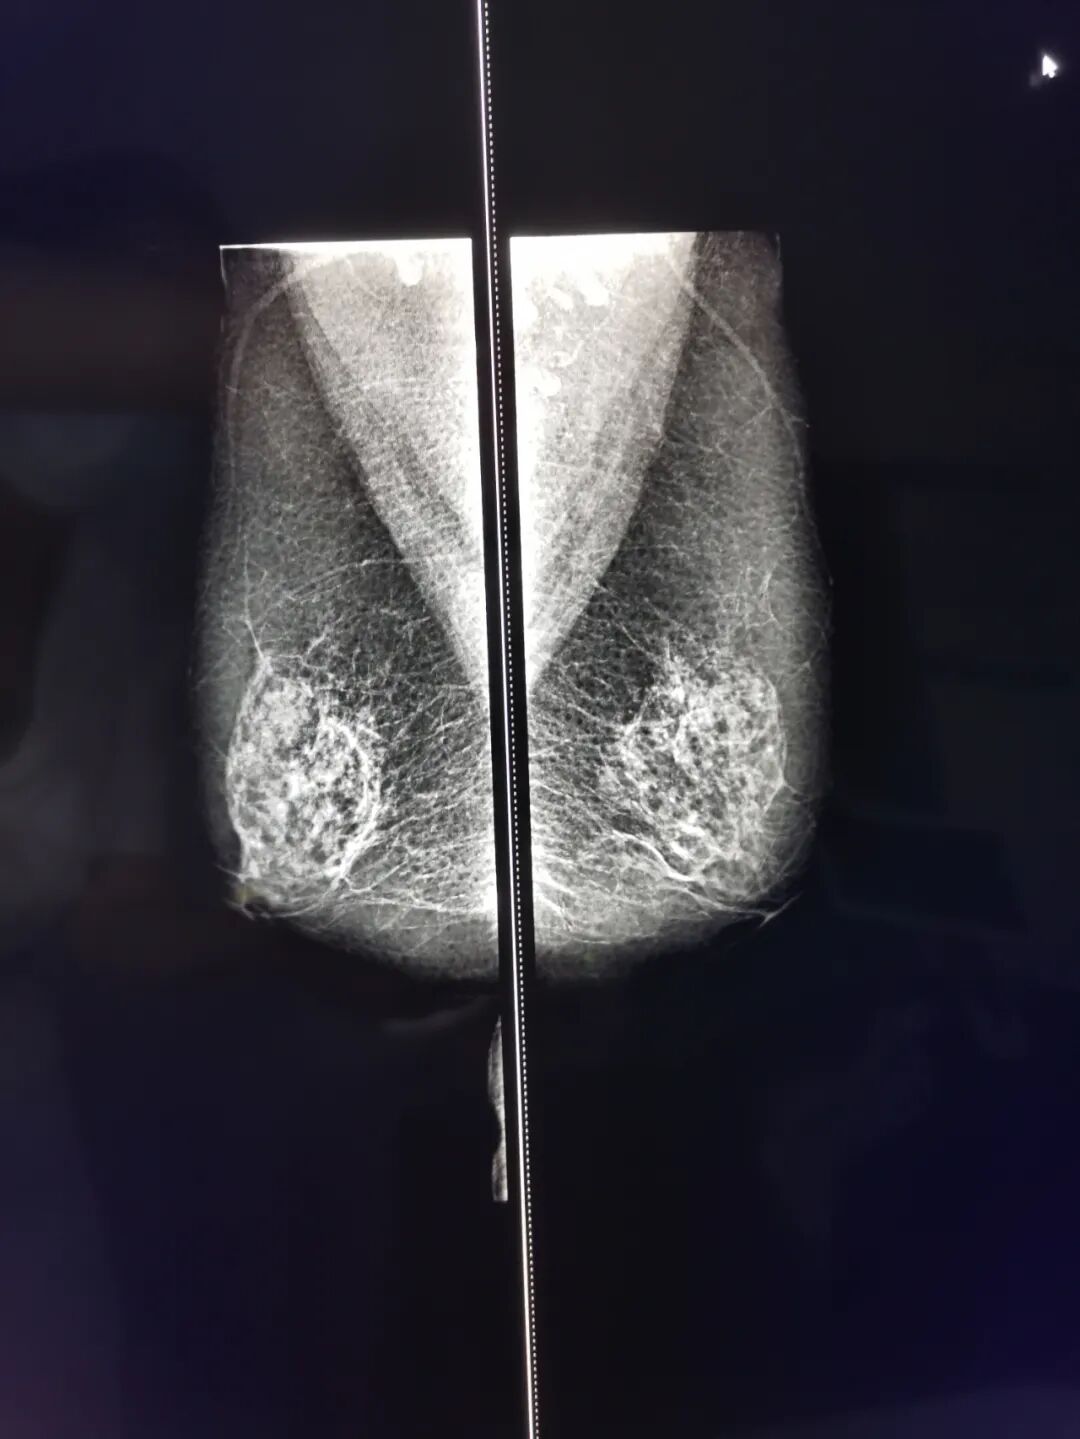

乳腺钼靶检查注意事项

1、检查时需要将上衣脱掉,请选择穿戴易于脱、穿的衣裤。避免穿无法将上衣独立脱掉的连衣裙或连体裤,如不能独立完成穿脱衣动作,需家属陪同;

2、检查时必须完全脱去上衣,不能佩戴项链、耳环等金属饰品;

3、优质的摄片效果离不开良好的乳腺组织压迫。为了能清楚呈现深部组织的影像,减少辐射剂量,技术人员会尽量压扁乳房。压迫使您感到有压力或有些疼痛,但每次压迫时间一般不超过一分钟,请您放松情绪,保持身体静止直至压迫解除,如移动身体可能需要二次检查;

4、尽量选择经期后10天左右进行检查。

乳腺钼靶x线摄影是目前诊断乳腺疾病的首选最简便、最可靠的检查手段,具有全面直观、操作简单、无创安全和费用低廉等特点,已成为公认的乳腺癌临床常规检查和乳腺癌预防普查的最好方法之一。